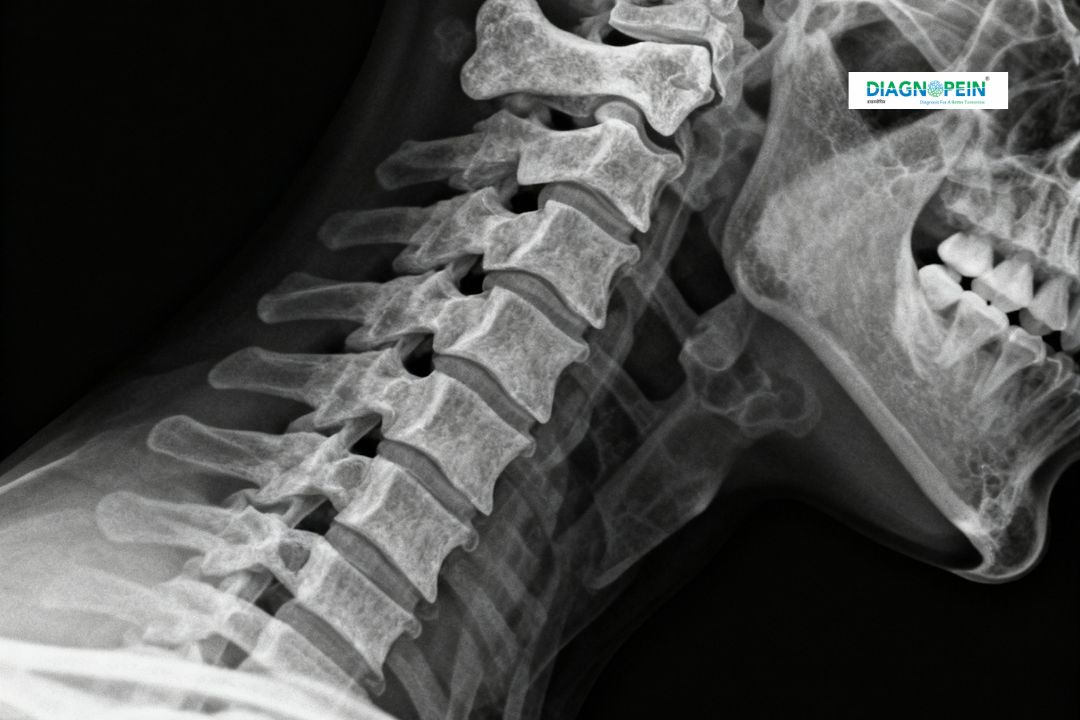

An X-Ray Cervical Spine Oblique is a specialized imaging test used to evaluate the vertebrae, joints, and nerve passages in the neck. This X-ray view helps doctors detect conditions affecting the cervical spine such as disc problems, arthritis, spinal misalignment, and nerve compression.

At Diagnopein, Karad’s trusted diagnostic center, we use advanced digital radiography technology to ensure high-quality cervical spine imaging with minimal radiation exposure. The oblique view offers a detailed look at the intervertebral foramina—spaces where the spinal nerves exit—making it crucial in diagnosing nerve root compression.

The cervical spine supports head movement and protects vital nerves connecting the brain and body. A general X-ray may not always show the side openings or nerve channels clearly, which is why an oblique view is performed.